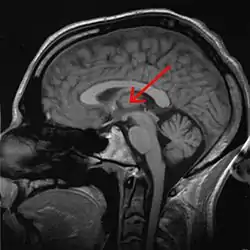

Thalamus

The thalamus (from Greek θάλαμος, "chamber")[1] is a large mass of gray matter located in the dorsal part of the diencephalon (a division of the forebrain). Nerve fibers project out of the thalamus to the cerebral cortex in all directions, allowing hub-like exchanges of information. It has several functions, such as the relaying of sensory signals, including motor signals to the cerebral cortex[2][3] and the regulation of consciousness, sleep, and alertness.[4]

![]() Thalamus marked (MRI cross-section) | |